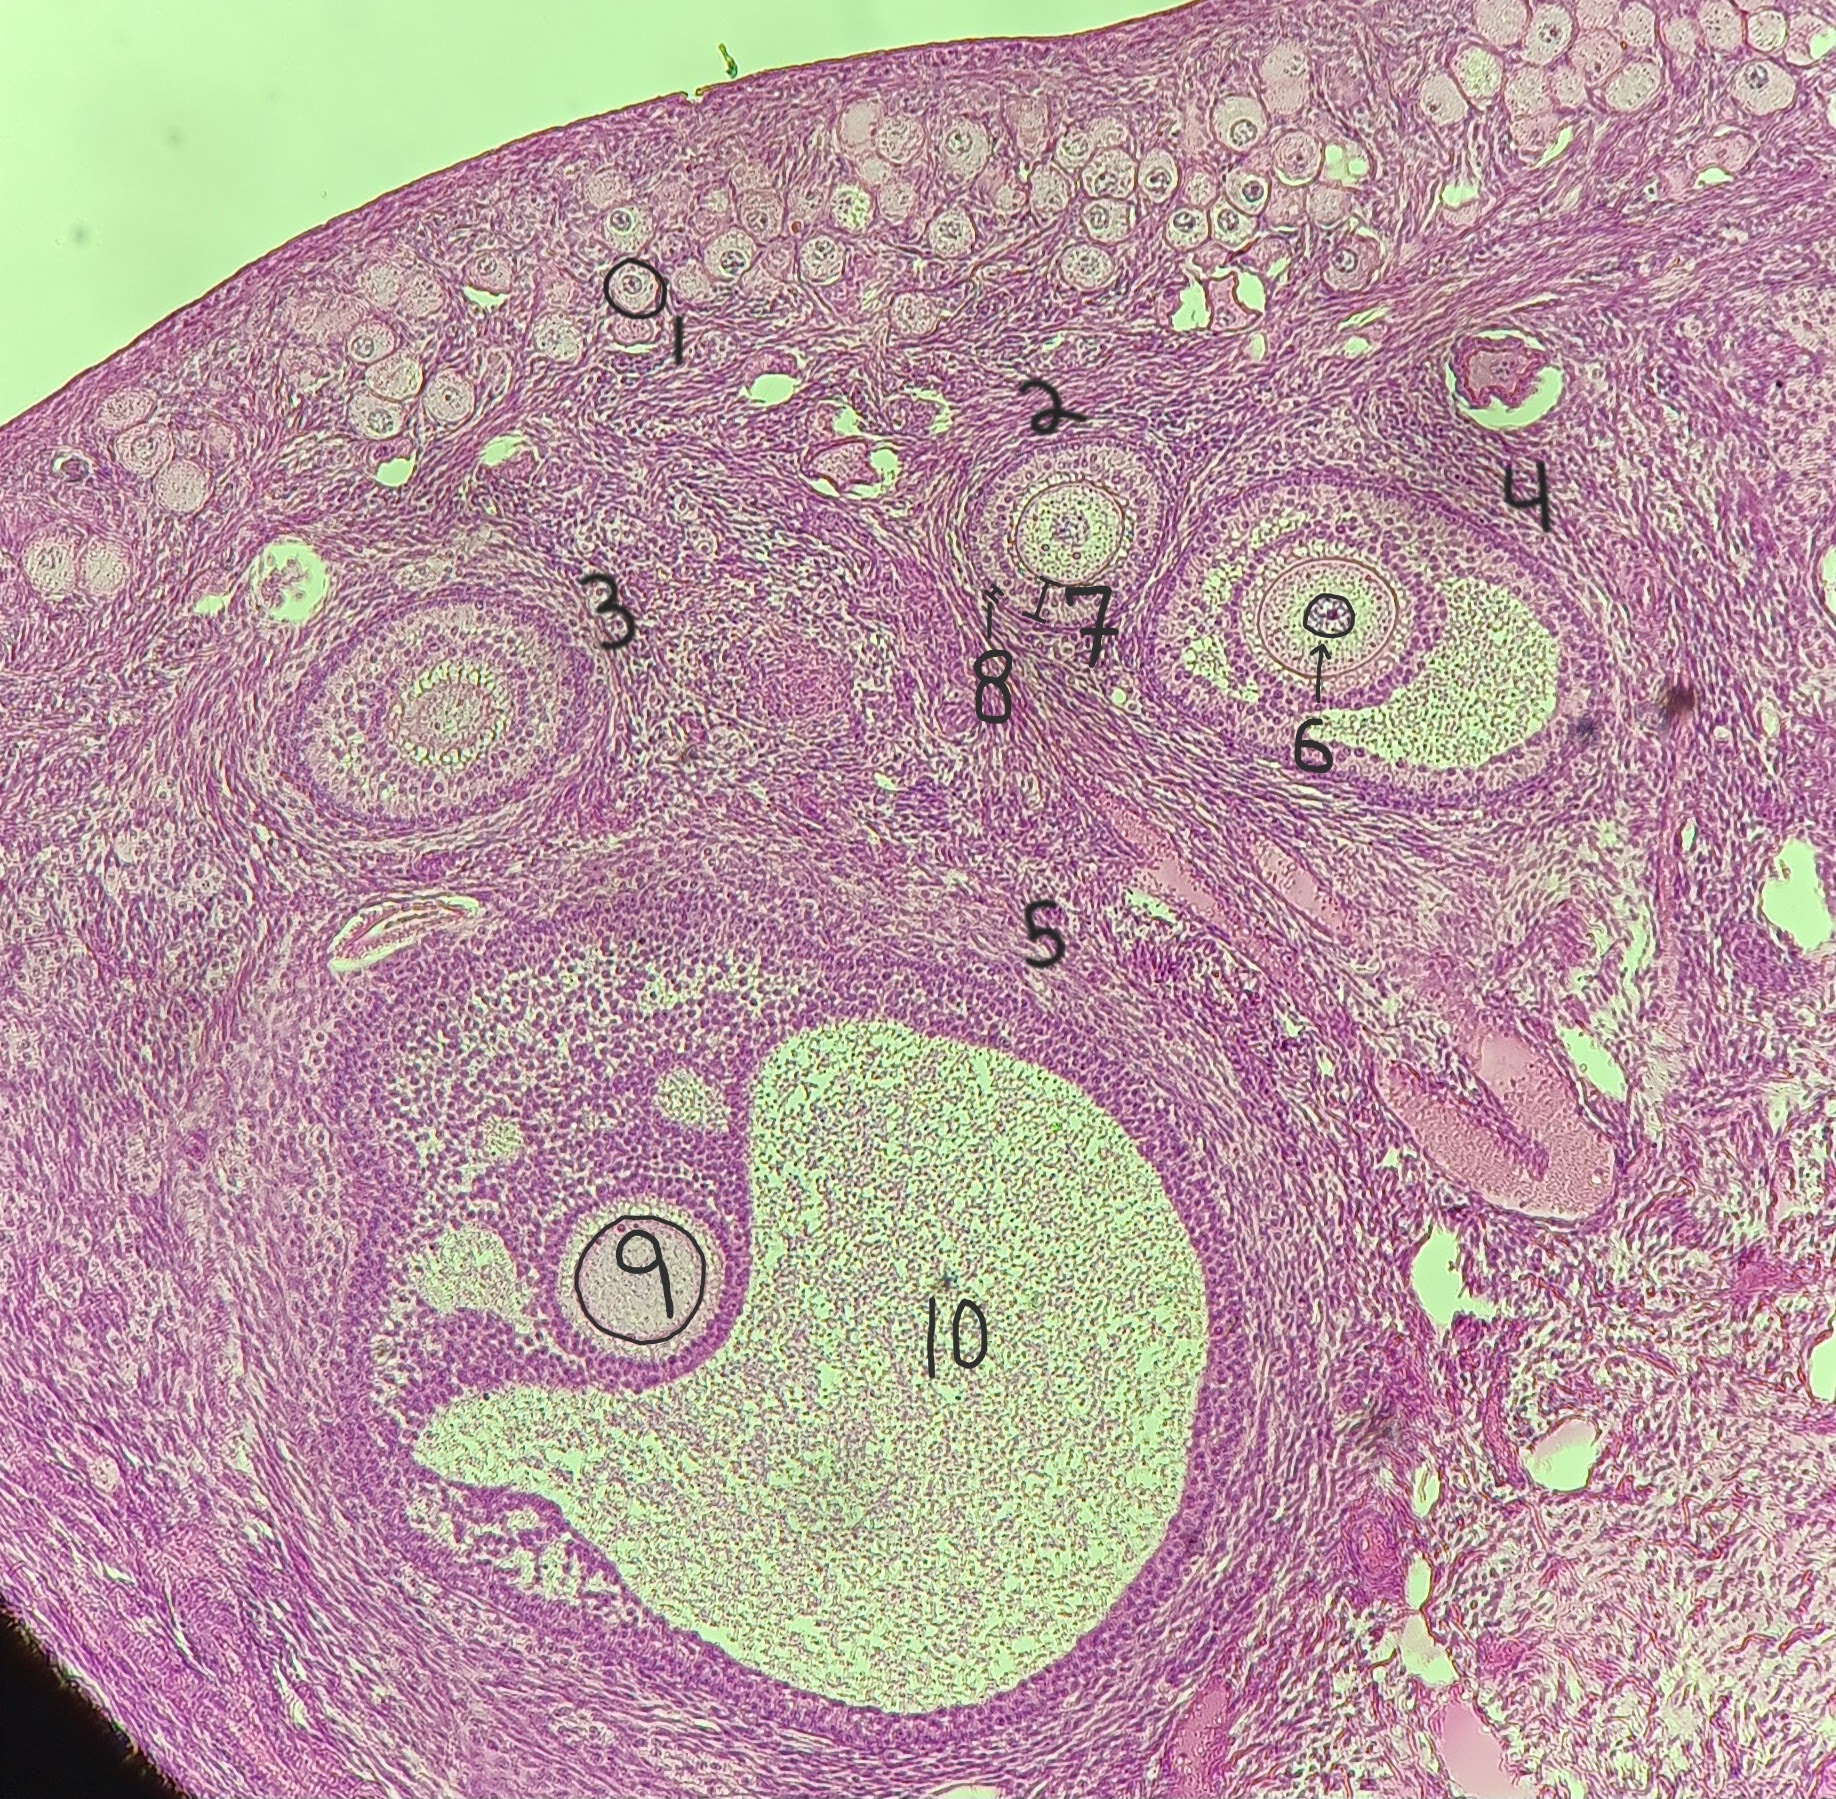

Primordial follicle

1

Primordial follicle

Primordial follicle

1

Primary follicle

2

Primary follicle

Primary follicle

2

Secondary follicle

3

Secondary follicle

Secondary follicle

3

Tertiary follicle

4

Tertiary follicle

4

Mature follicle

5

Mature follicle

Mature follicle

7

Antrum

10

Zona pellucida

9

Theca folliculi

8